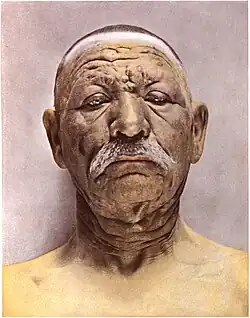

Face mildly deformed by leprosy

Face mildly deformed by leprosy